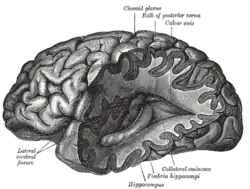

Quantitative trait loci (QTL) mapping is another statistical method used to determine the chromosomal positions of a set of genes responsible for a given trait. By identifying specific genetic markers for the genes of interest in a recombinant inbred strain, the amount of interaction between these genes and their relation to the observed phenotype can be determined through complex statistical analysis. In a neurogenetics laboratory, the phenotype of a model organisms is observed by assessing the morphology of their brain through thin slices.[16] QTL mapping can also be carried out in humans, though brain morphologies are examined using nuclear magnetic resonance imaging (MRI) rather than brain slices. Human beings pose a greater challenge for QTL analysis because the genetic population cannot be as carefully controlled as that of an inbred recombinant population, which can result in sources of statistical error.[17]

A great deal of research has been done on the effects of genes and the formation of the brain and the central nervous system. The following wiki links may prove helpful: